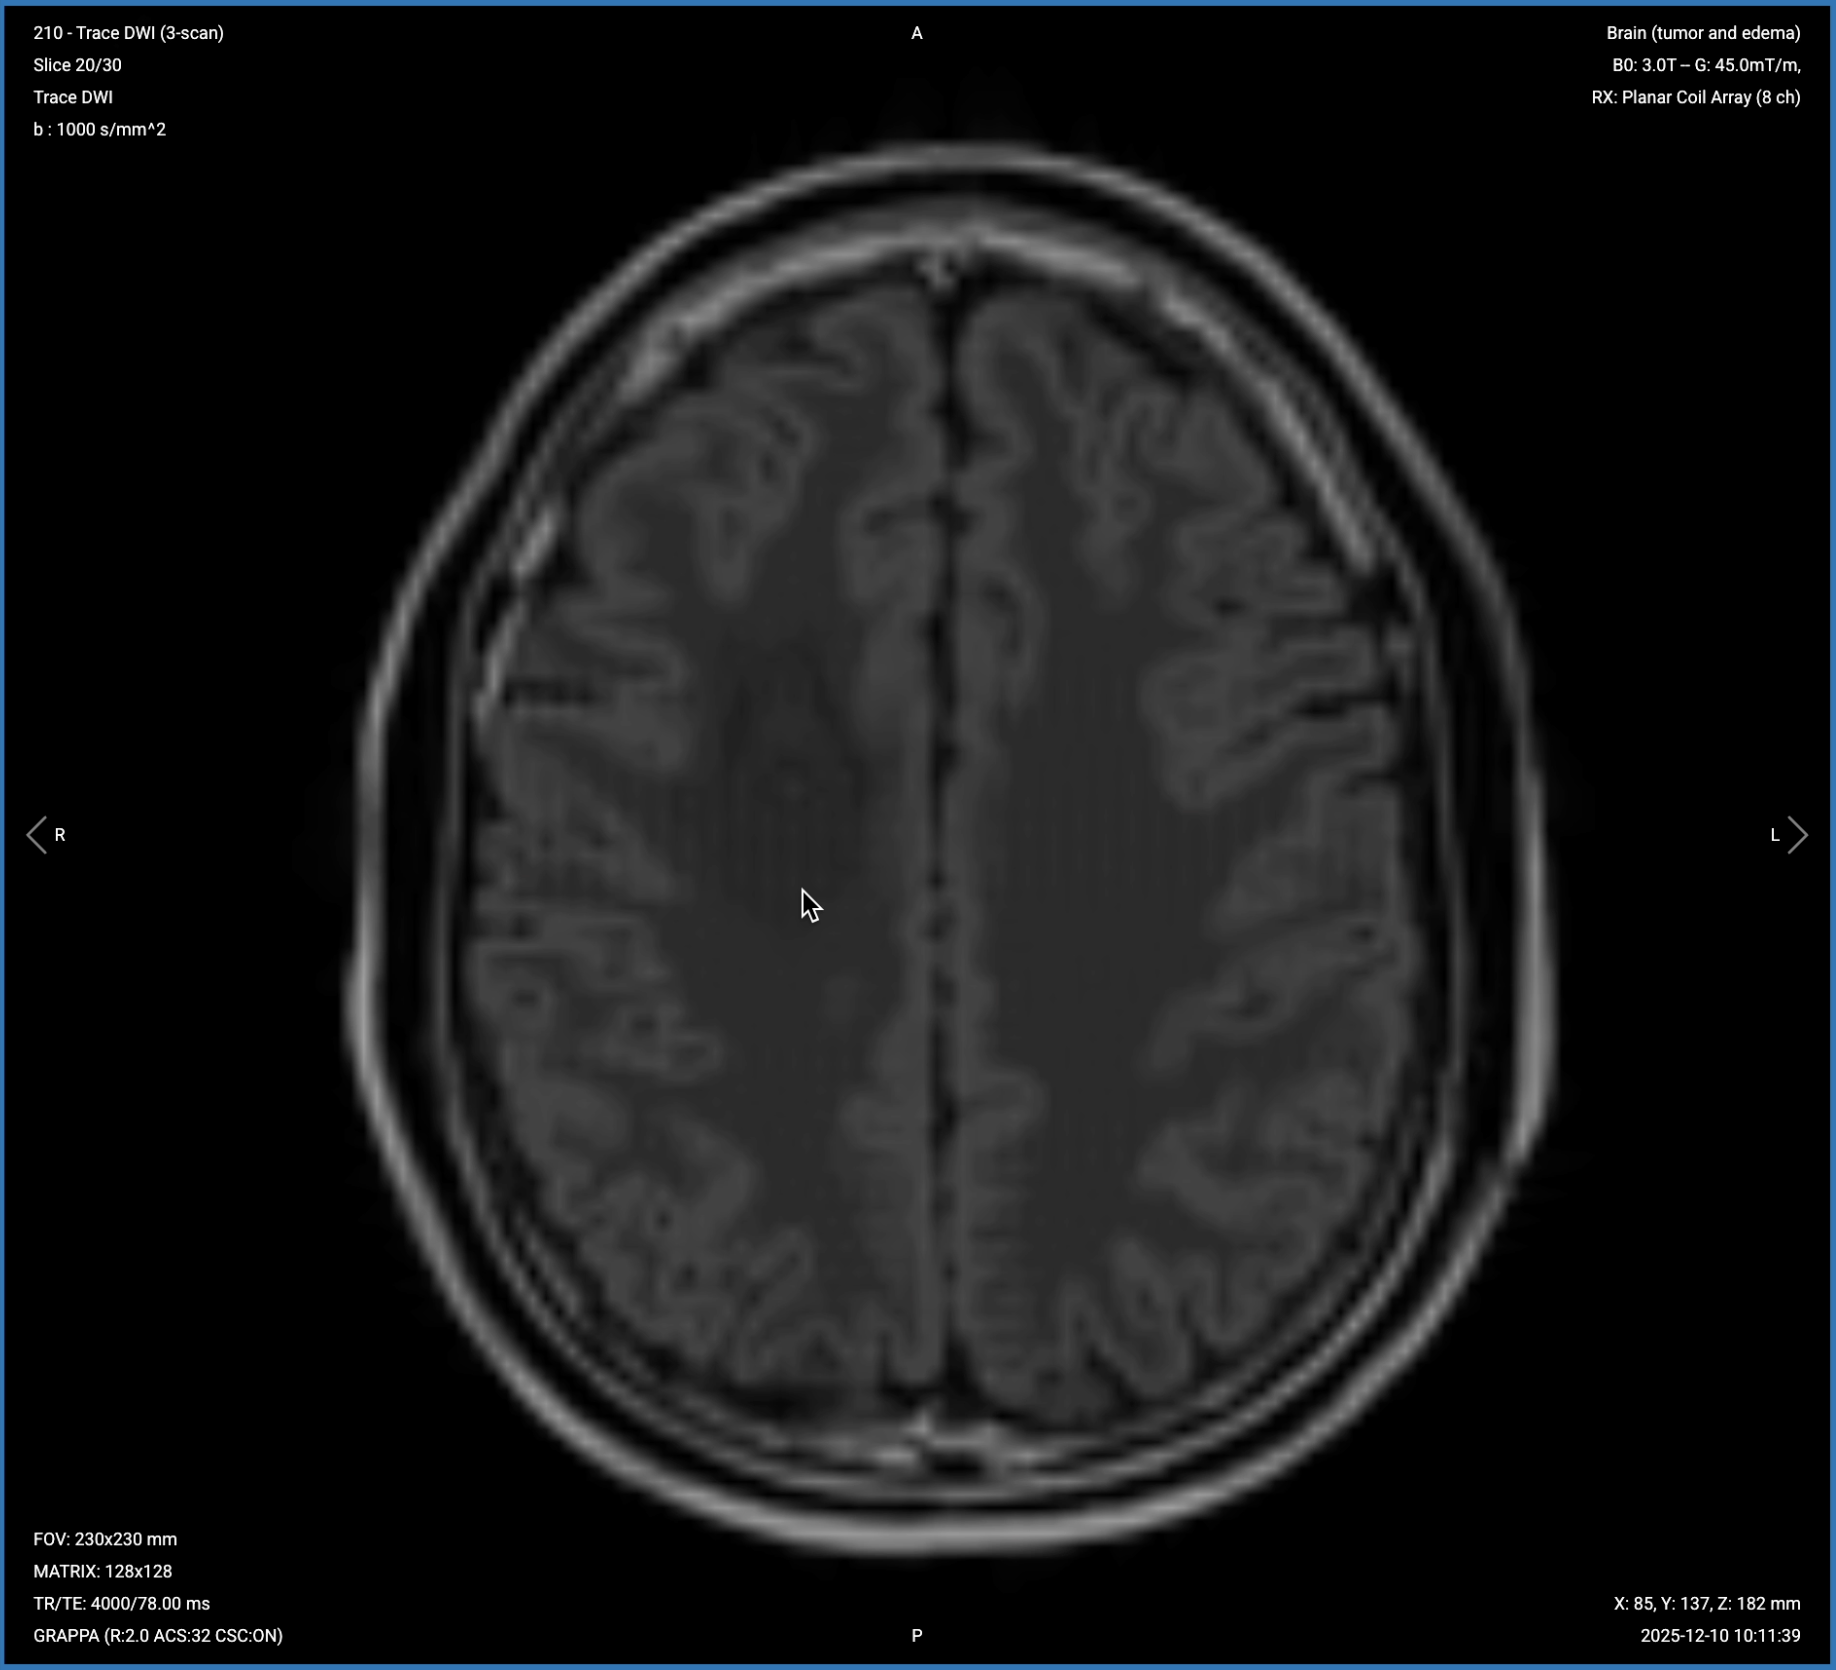

4. Planning Axial Diffusion-Weighted Imaging (DWI) with ADC Map

✅ Correct Planning:

Correct Planning Axial Diffusion-Weighted Imaging (DWI) with ADC Map

Planning Instructions:

• Use the corpus callosum as the anatomical reference.

• Align the slices as follows:

• Sagittal Localizer: Use the same axial prescription as T2/FLAIR, but position the slice package slightly upward and rotate clockwise to avoid paranasal sinuses and oral cavity. Including these air-filled areas causes susceptibility artifacts.

• Coronal Localizer: Perpendicular to the mid-sagittal line.

• Use appropriate geometry parameters:

• Slice number: 25–30 to cover the brain while avoiding air-tissue interfaces inferiorly.

• Slice thickness: 3–4 mm to match other axial sequences when possible.

• Slice gap: 0–1 mm to maintain continuity between slices.

• Set the fold-over direction (phase encoding) to right-left (RL) to contain geometric distortions to RL direction rather than diagnostically critical AP axis.

• Activate fat suppression (spectral-based), which is required for DWI.

• Set b-values to 0 and 1,000 s/mm² for standard tumor assessment.

• Turn ADC map output to ON to quantify water diffusion and differentiate tumor cellularity.

Diffusion-Weighted Imaging (DWI) with ADC – Assesses Tumor Cellularity

Diffusion-weighted imaging detects restricted water molecule movement in tissue. High cellularity restricts diffusion, causing bright signal on DWI and dark signal on ADC maps.

In brain tumor imaging, DWI helps assess tumor cellularity and differentiate between lesion types.

• High diffusion signal and low ADC indicates restricted diffusion, or high cellularity. This can be a sign of high-grade gliomas, lymphomas, or abscesses.

• Low diffusion signal and high ADC indicates facilitated diffusion, or low cellularity. This can be a sign of necrosis, cystic components, vasogenic edema, or low-grade lesions.

This sequence is crucial for distinguishing high-grade gliomas and lymphomas from low-grade tumors, cysts, or necrotic areas. DWI also helps differentiate abscesses (which restrict diffusion) from cystic tumors (which don't).

We acquire this sequence in the axial plane to match other sequences, though with modified coverage to avoid air-tissue interfaces at the skull base that cause severe susceptibility artifacts.

The DWI sequence generates 3 types of images from a single acquisition:

1. b=0 Image (Baseline)

The b=0 image shows tissue without diffusion weighting, essentially a T2-weighted image that serves as an anatomical reference.

Correct Image Example:

Axial DWI of brain, b=0 (baseline) – correct image example

2. True Diffusion Image (b=1000)

The true diffusion image shows areas of restricted water diffusion as bright signal. Select the slice where the tumor is visible to assess diffusion characteristics.

Axial DWI of the brain, True Diffusion Image (b=1000) – correct image example

3. ADC Map (Apparent Diffusion Coefficient)

The ADC map quantifies diffusion, where restricted diffusion appears dark and facilitated diffusion appears bright. This confirms whether bright or dark areas on DWI represent true restriction or facilitation.

ADC Map (Apparent Diffusion Coefficient) – correct image example

Things to Look for in DWI and ADC:

• High DWI signal + Low ADC = Restricted diffusion = High cellularity (glioma, lymphoma, abscess).

• Low DWI signal + High ADC = Facilitated diffusion = Low cellularity (necrosis, cystic components, edema, low-grade lesions).

• Diffusion pattern across the mass – uniform or heterogeneous.

• Agreement between DWI and ADC – they should show opposite patterns for true restriction or facilitation.